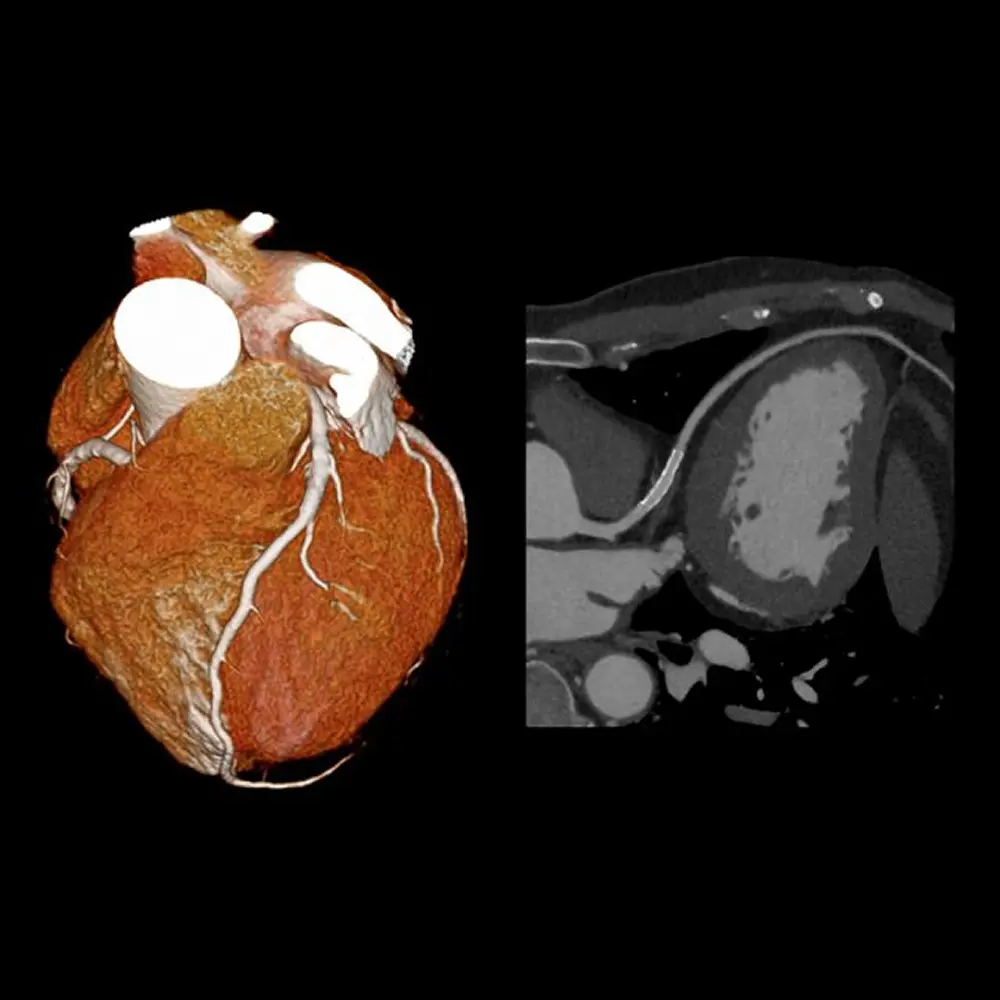

Aquilion Lightning SP è un sistema CT elicoidale multistrato che supporta l’imaging di tutto il corpo e permette di effettuare esami tomografici in modo molto più rapido ed efficiente. Il sistema impiega le tecnologie più innovative per la riduzione della dose e una rapida ricostruzione per ridurre al minimo l’esposizione del paziente e il tempo necessario per la diagnosi.

Il sistema è progettato per funzionare in modo affidabile ed efficiente, producendo immagini di alta qualità che aiutano ad accelerare la diagnosi e il trattamento in un ambiente frenetico.